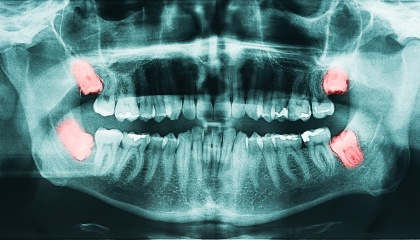

Wisdom Teeth Removal Made Easy

before

after

During your first visit, we'll conduct a thorough review of your medical history and engage in a comprehensive discussion about the wisdom teeth removal process. We'll utilize X-rays to assess the position and condition of your wisdom teeth, enabling us to create a personalized treatment plan tailored to your specific needs and anatomical considerations. This plan will outline the associated costs, timeline, and steps involved in the procedure. We also encourage you to ask any questions you may have; we're committed to addressing any concerns you might have and ensuring you feel fully informed throughout the process.